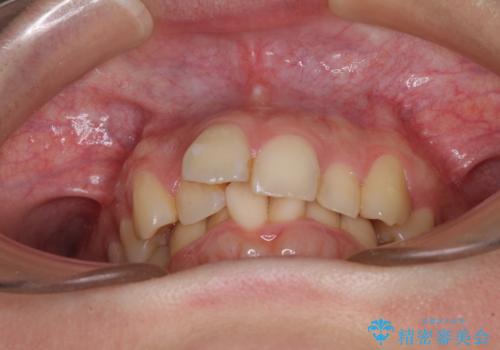

- 前歯のデコボコを気にして来院された患者様です。

上下の前歯にデコボコがあり、更にはディープバイトにより下顎前歯の大半が隠れている状態でした。

上顎左右第一小臼歯の2本を抜歯し、ワイヤー装置を使用して咬み合わせ高さを改善しながら、歯列を整えて行くこととしました。